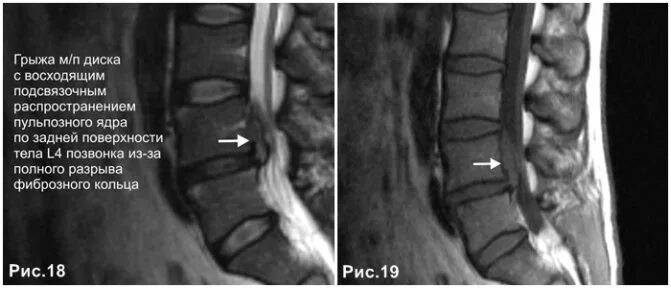

Протрузия в дуральном